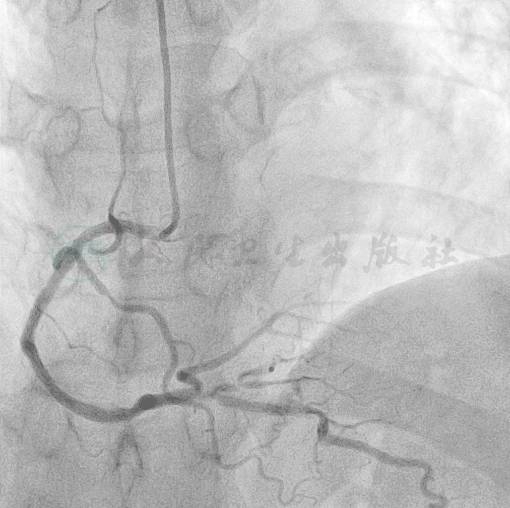

图4 右冠经间隔支途径及心尖途径向前降支提供良好的侧支循环

造影结果:前降支开口100%闭塞,隐约可见微小残端(图1);回旋支远段70%狭窄(图2);右冠后降支开口85%狭窄(图3),右冠经间隔支途径及心尖途径向前降支提供良好的侧支循环(图4)。